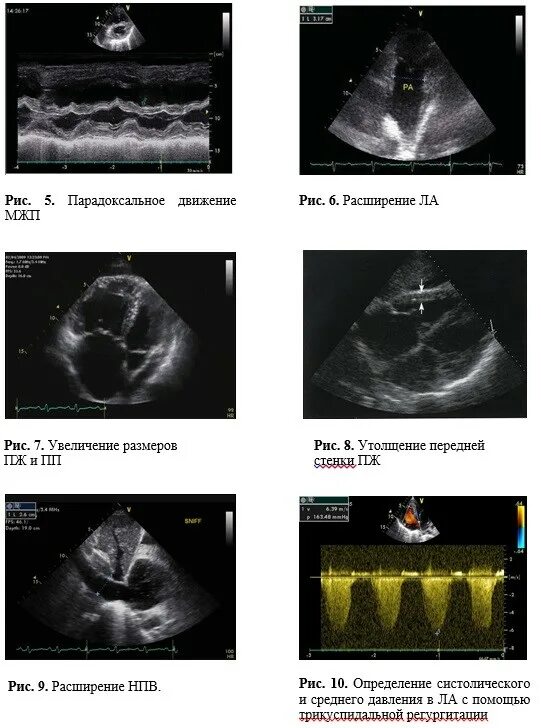

Эхокг сдла